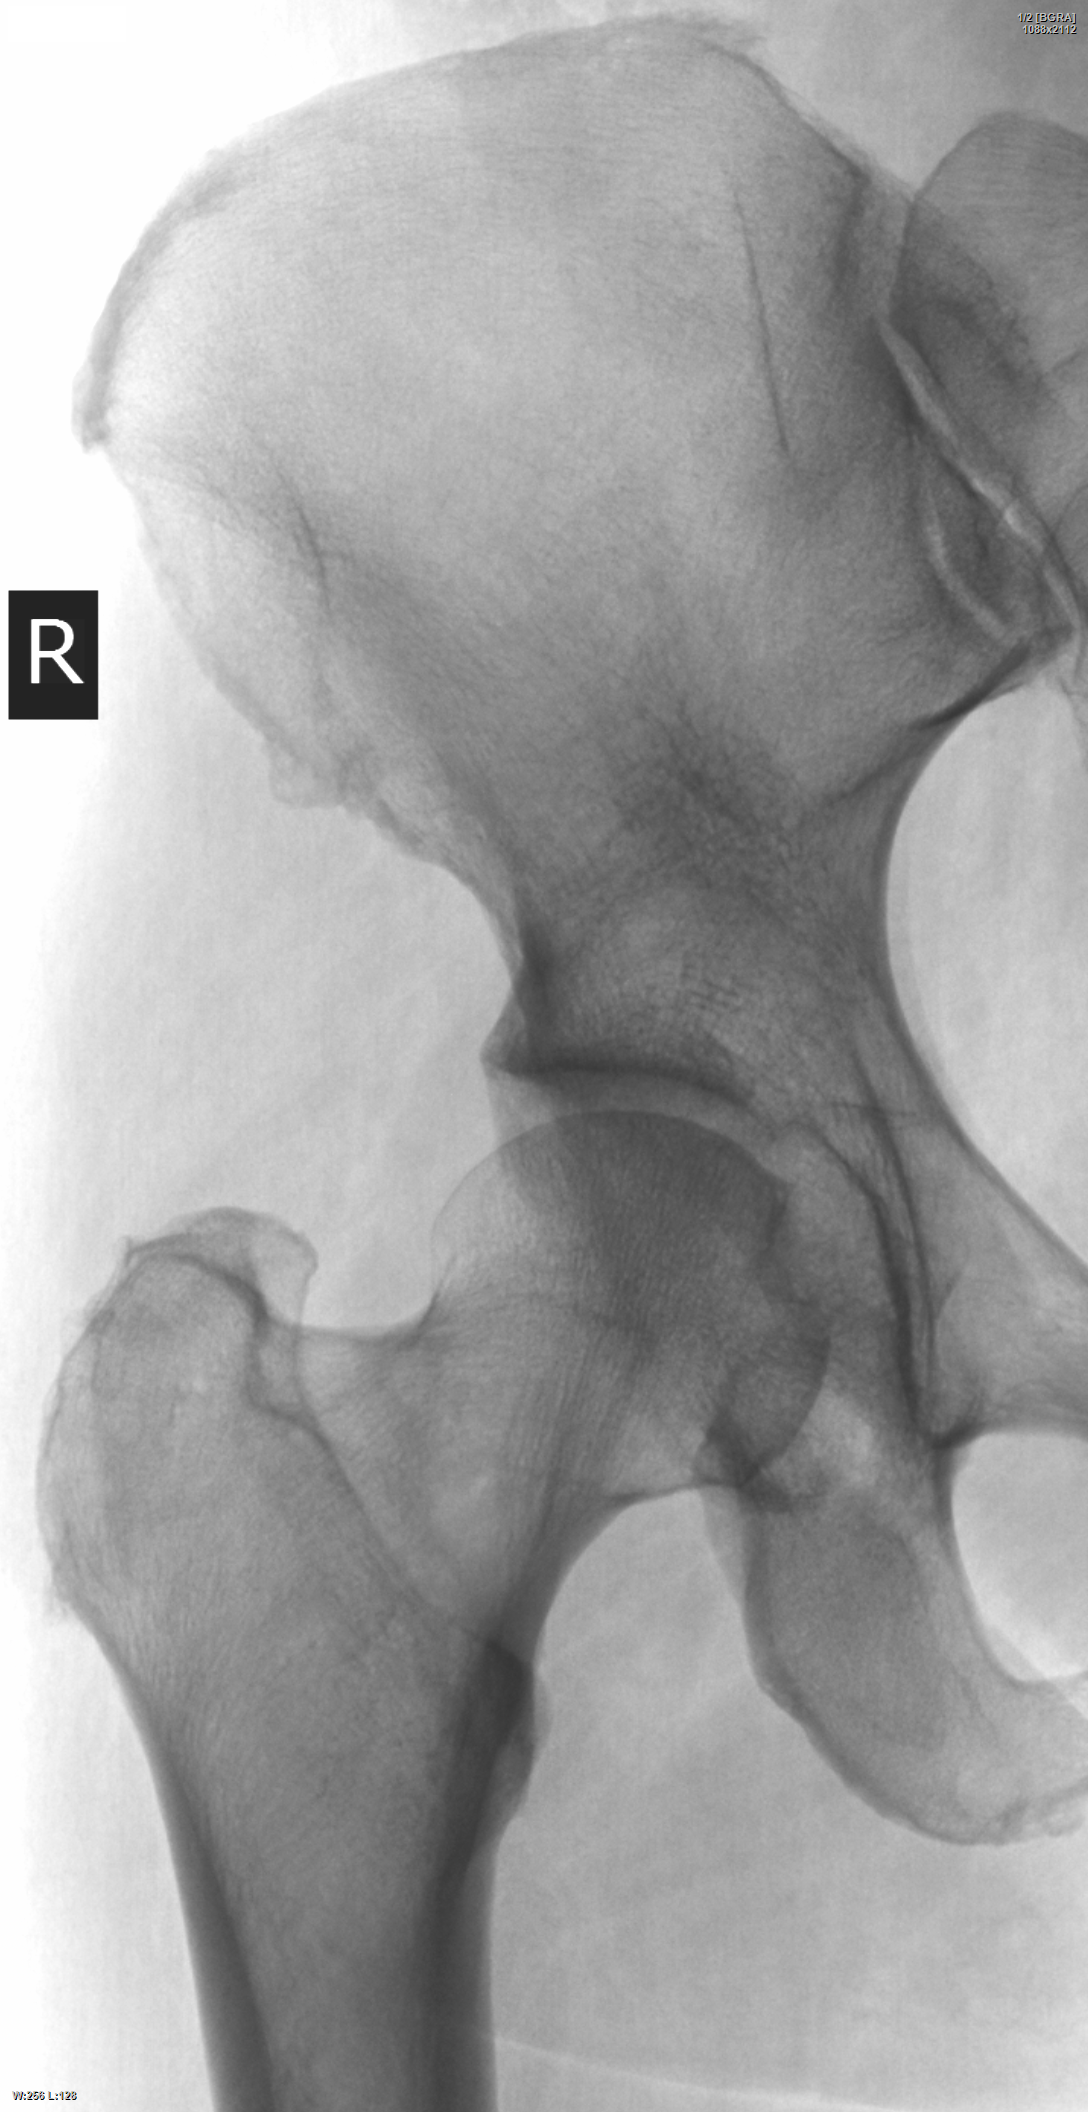

Женщина, 59 лет. В направлении рентгенография тазобедренного сустава и коленного сустава. Обоих справа. Написал остеопороз шейки бедра.

Норма. В шейке. Мелкие кисты наружного края крыши вертлужной впадины.

В шейке по 1 проекции трактую как наложение фигуристости мягких тканей)). Нарушения костной структуры шейки не вижу.

Хорошо бы, чтобы так было. Только дама эта была не так чтобы фигуриста, и мягкие ткани немного от шейки правее. Может, с учётом уменьшения разрешения при загрузке на сайт снимок слегка потерял.

Максималист прав, шейка тут весьма и весьма "стремная" и в первую очередь - метастазы исключаем.....